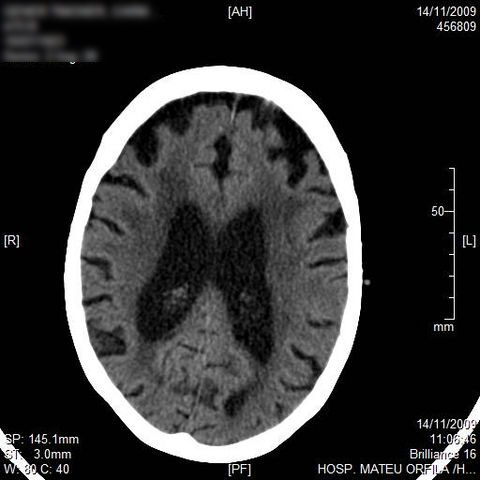

AVC amplio de territorio de A. cerebral media